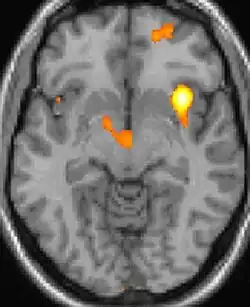

Neuro-imagerie

La tomographie par émission de positons (TEP) montre les zones du cerveau étant activées durant la douleur

Les images par tomographie à émission de positron indiquent les régions du cerveau qui sont activées lors de la douleur, par rapport aux périodes sans douleur. Elles montrent les régions du cerveau qui sont toujours actives durant la douleur en jaune/orange (appelé "matrice-douleur"). La zone au centre (dans les trois vues) est spécifiquement activée uniquement pendant la crise. Les photos sur la ligne du bas (effectuées par VBM) montrent les différences structurelles entre les patients souffrant d'AVF et des personnes saines : seulement une partie de l'hypothalamus est différente[50],[51].